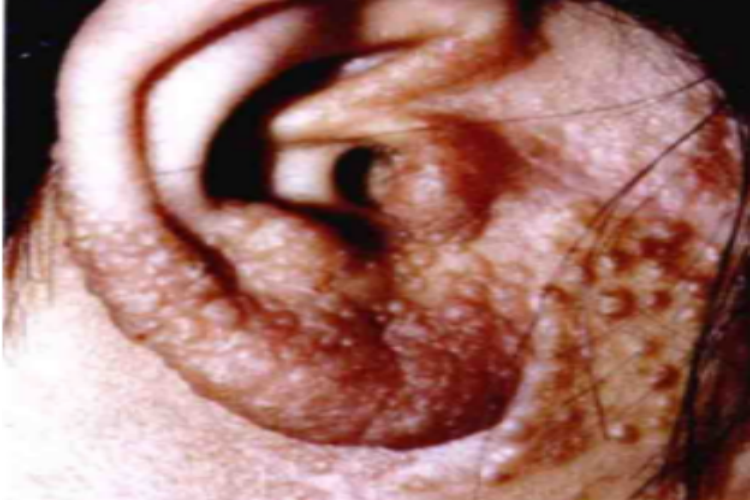

无绿藻病的皮肤损害可发生在耳部,临床可表现为局部出现米粒大小的丘疹、结节,数量较多,像很多小疙瘩,皮损会互相融合,为了避免继发感染,不要用力抓挠皮损部位。